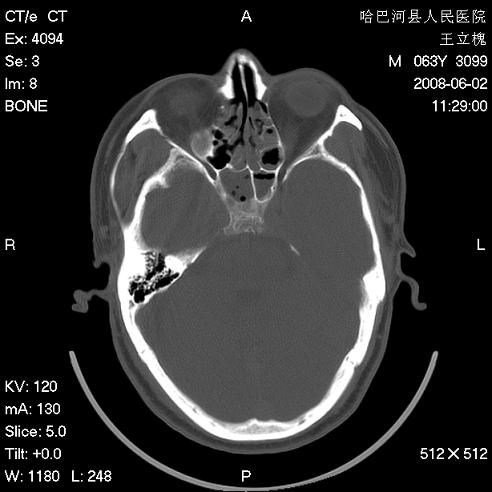

标题: CT13803:反复性鼻塞、流涕一年余 [打印本页]

标题: CT13803:反复性鼻塞、流涕一年余

副鼻窦炎,右上额窦积脓。左眼肌锥内见致密影,视神經受压

1.全组副鼻窦炎2.双侧上颌窦积液

1)全副鼻窦炎(左侧上颌窦黏膜下囊肿或息肉)。2)左眼眶肌锥内不规则小结节状软组织密度影;考虑为小血管瘤可能。建议行ct增强扫描检查。

全组副鼻窦炎,左侧肌锥内不规则形软组织肿块影,与眼外肌密度相当,左侧视神经受压,肿块与视神经及眼外肌分界清晰,眼外肌无增粗,眶壁无破坏,球后脂肪间隙不模糊,考虑良性改变,小血管瘤或神经源性肿瘤可能,建议增强扫描。

谢谢,增强扫描做了,眶内病灶与海绵窦同步明显强化,血管瘤